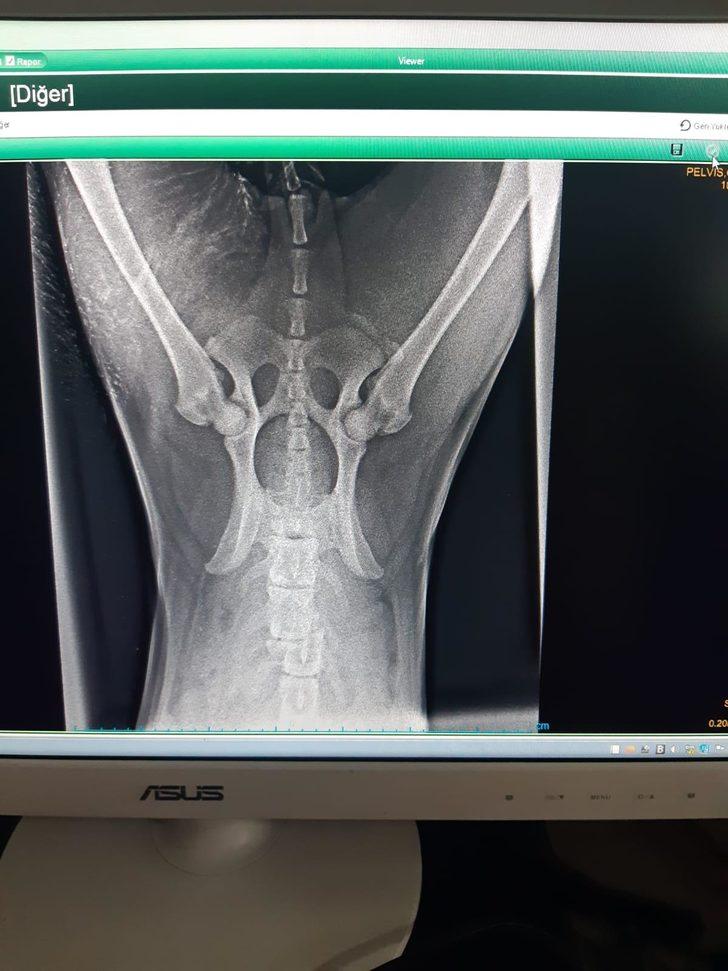

Olay, geçen 9 Ocak'ta, Kargı ilçesi Bahçelievler Mahallesi'nde meydana geldi. Betül Özcan'a ait Kangal cinsi köpeğe sokakta otomobil çarptı. Sürücü kaçarken yaralı köpek sahibi tarafından Ankara'da bir kliniğe götürüldü. Köpek, tüm müdahalelere rağmen 3 gün sonra öldü. Betül Özcan'ın şikayeti üzerine polis kaçan sürücüyü tespit etti. Sürücü Durmuş Mustafa E. (21) hakkında 'mala zarar verme' suçundan soruşturma başlatıldı.

Köpeğini kaybetmenin üzüntüsünü yaşayan evli ve 2 çocuk annesi Betül Özcan, klinikten gelen haberle bir kez daha çaresiz kaldı. Özcan'a, köpeğini tedavisi için götürdüğü klinikten 5 bin liralık fatura çıkarıldı. Ücreti ödeyecek durumunun olmadığını anlatan Betül Özcan, "Köpeğimi gezmesi için sokağa salmıştım. Uzun süre gelmeyince köpeğime bakmaya gittim. Gördüğüm manzara korkunçtu. Evladım gibi gördüğüm köpeğime bir otomobil çarpıp kaçmıştı. Durumu ağır olduğu için de kendi aracımızla Ankara'da bir kliniğe götürdük. 3 gün tedavi altında tutuldu ve öldü. Köpeğime çarpıp ölümüne neden olan otomobil sürücüsüne ceza verilmedi. Bana da tedavi masrafı olarak 5 bin lira borç çıkarıldı. Benim parayı ödeme gücüm yok. Babamın gözleri görmüyor. Ölen köpeğim onun eli ayağıydı" dedi.